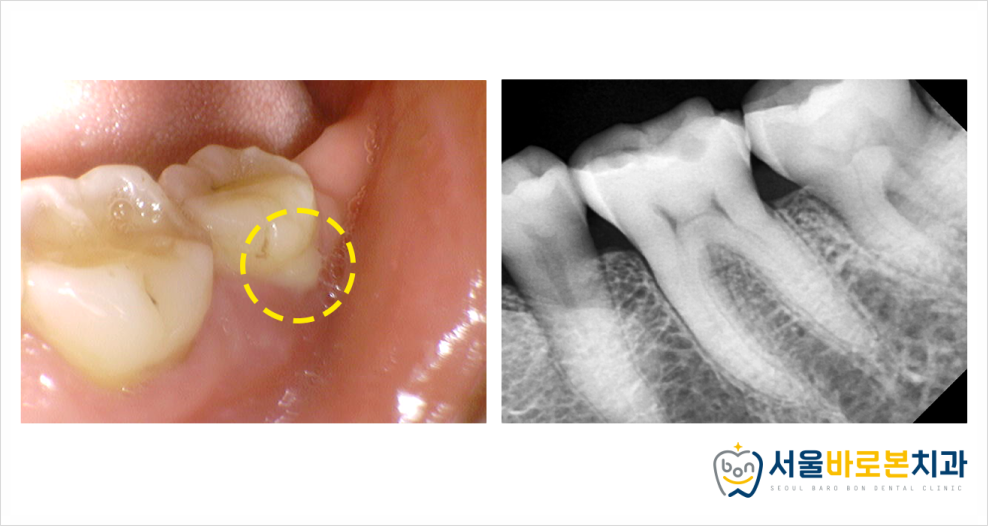

우선 입안 상태부터

꼼꼼하게 체크해보았는데요.

저작하는 힘이 굉장히 강하여

앞니와 어금니 할 것 없이

전체적으로 치아들이 닳아있는

교모된 양상을 보이고 있었습니다.

.

몇몇 치아들은 치아 내부의 노란 층인

상아질까지 비추어 보이는 것을

확인할 수 있었답니다.

현재 노란색 표시의

왼쪽 아래 어금니 부위에 통증이 있는 상황으로,

이렇게 보기에는 교모되어 있는 상태 외에는

큰 문제가 없어 보이긴 합니다.

정밀한 체크를 위해

파노라마 사진을 촬영하여 체크를 해보았더니

가장 후방에 있는 치아는

잇몸 쪽으로 염증 소견이 보였습니다.

조금 더 자세하게 확인하기 위해

작은 사진도 함께 촬영해보았는데요.

더 자세하게 볼 수 있는

치근단 방사선 사진과

구강 내 사진을 촬영해보았고,

가장 후방의 치아를

정밀하게 체크해보니

고름이 나오는 것을

체크할 수 있었습니다.

치과 기구를 이용하여

가장 안쪽 큰 어금니의 잇몸을

조금씩 눌러만 보아도 위 사진처럼

고름이 올라오고 있는 상황이었는데요.